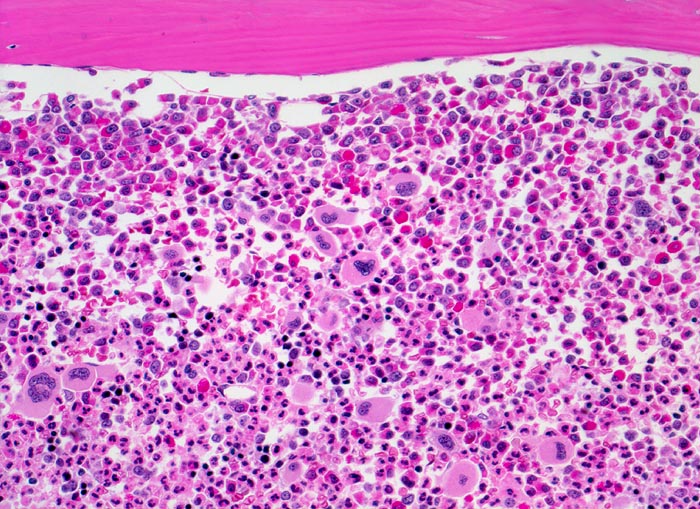

chronische myeloische Leukämie (CML)

Knochenmark, Beckenkamm

Extrem hyperzelluläres Knochenmark ohne Fettzellen. Hochgradig gesteigerte voll ausreifende neutrophile Granulopoese. Erkennbar sind verschiedene Reifungsstufen der Granulopoese, wobei die unreiferen Vorstufen (Myelozyten, Promyelozyten) bevorzugt entlang des Spongiosabälkchens paratrabekulär lokalisiert sind. Zur Mitte des Markraumes hin folgt die Reifungszone mit Prädominanz segmentkerniger Neutrophiler. Die normoblastäre Erythropoese ist fast vollständig verdrängt. Typisch ist die Vermehrung kleiner Megakaryozyten mit hypolobulierten Kernen.

Müdigkeit und Gewichtsverlust. Ausgeprägte Leukozytose, Basophilie und leichte Anämie. Palpable Milz.

200